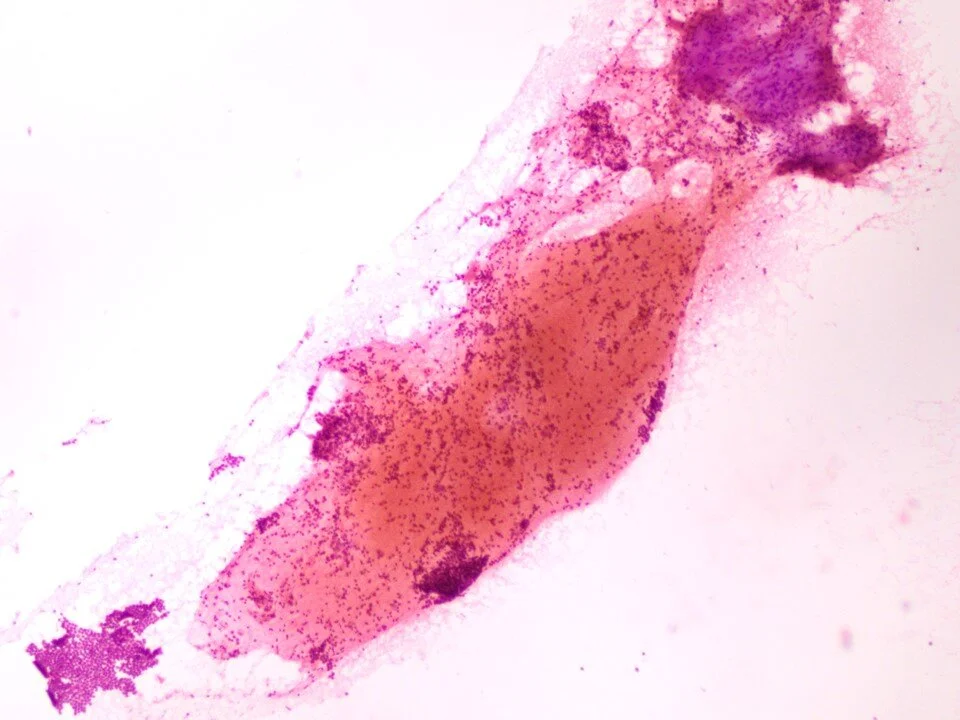

Pulmonary alveolar proteinosis